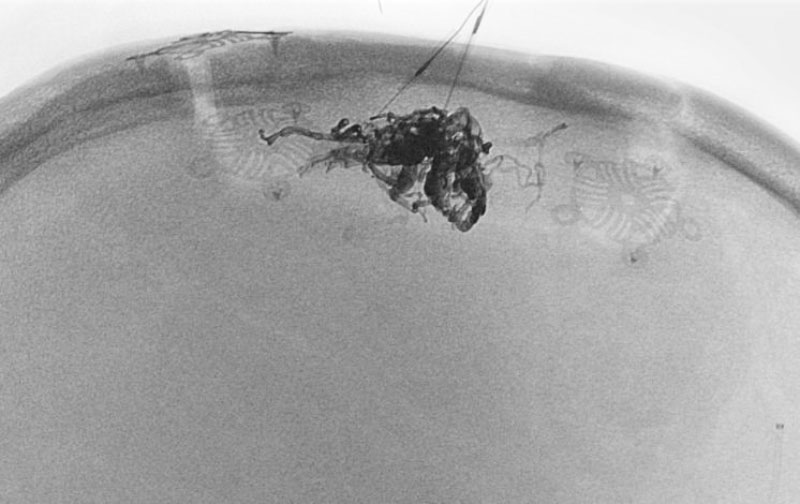

1585

'25年10月6日

脳動静脈奇形

50代

大阪府の病院

手術写真

治療

前